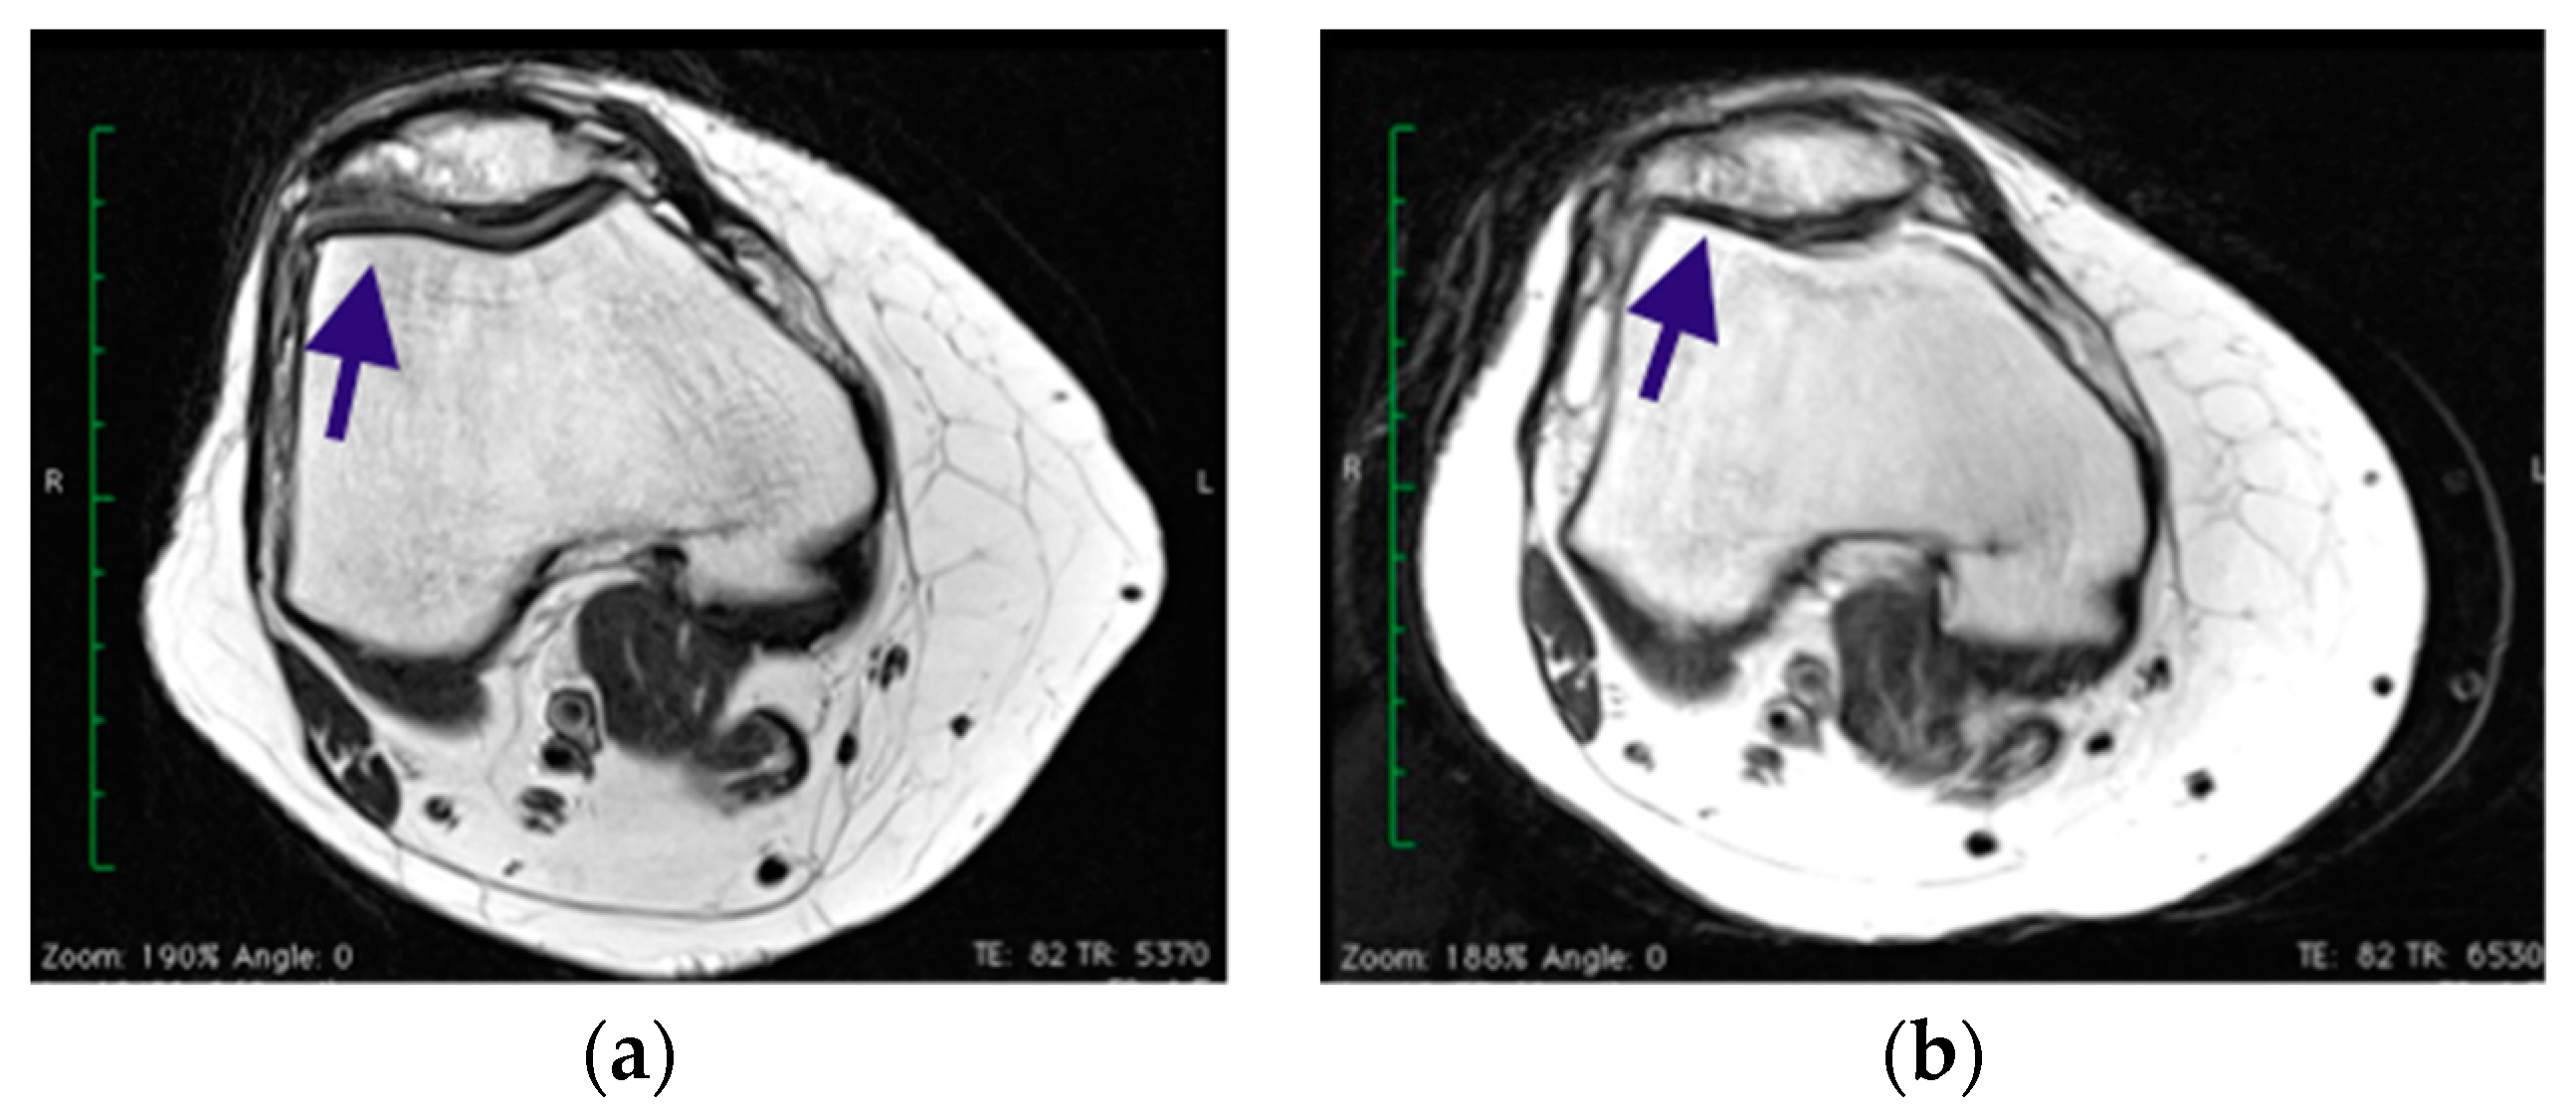

2.1. Surgical Procedure